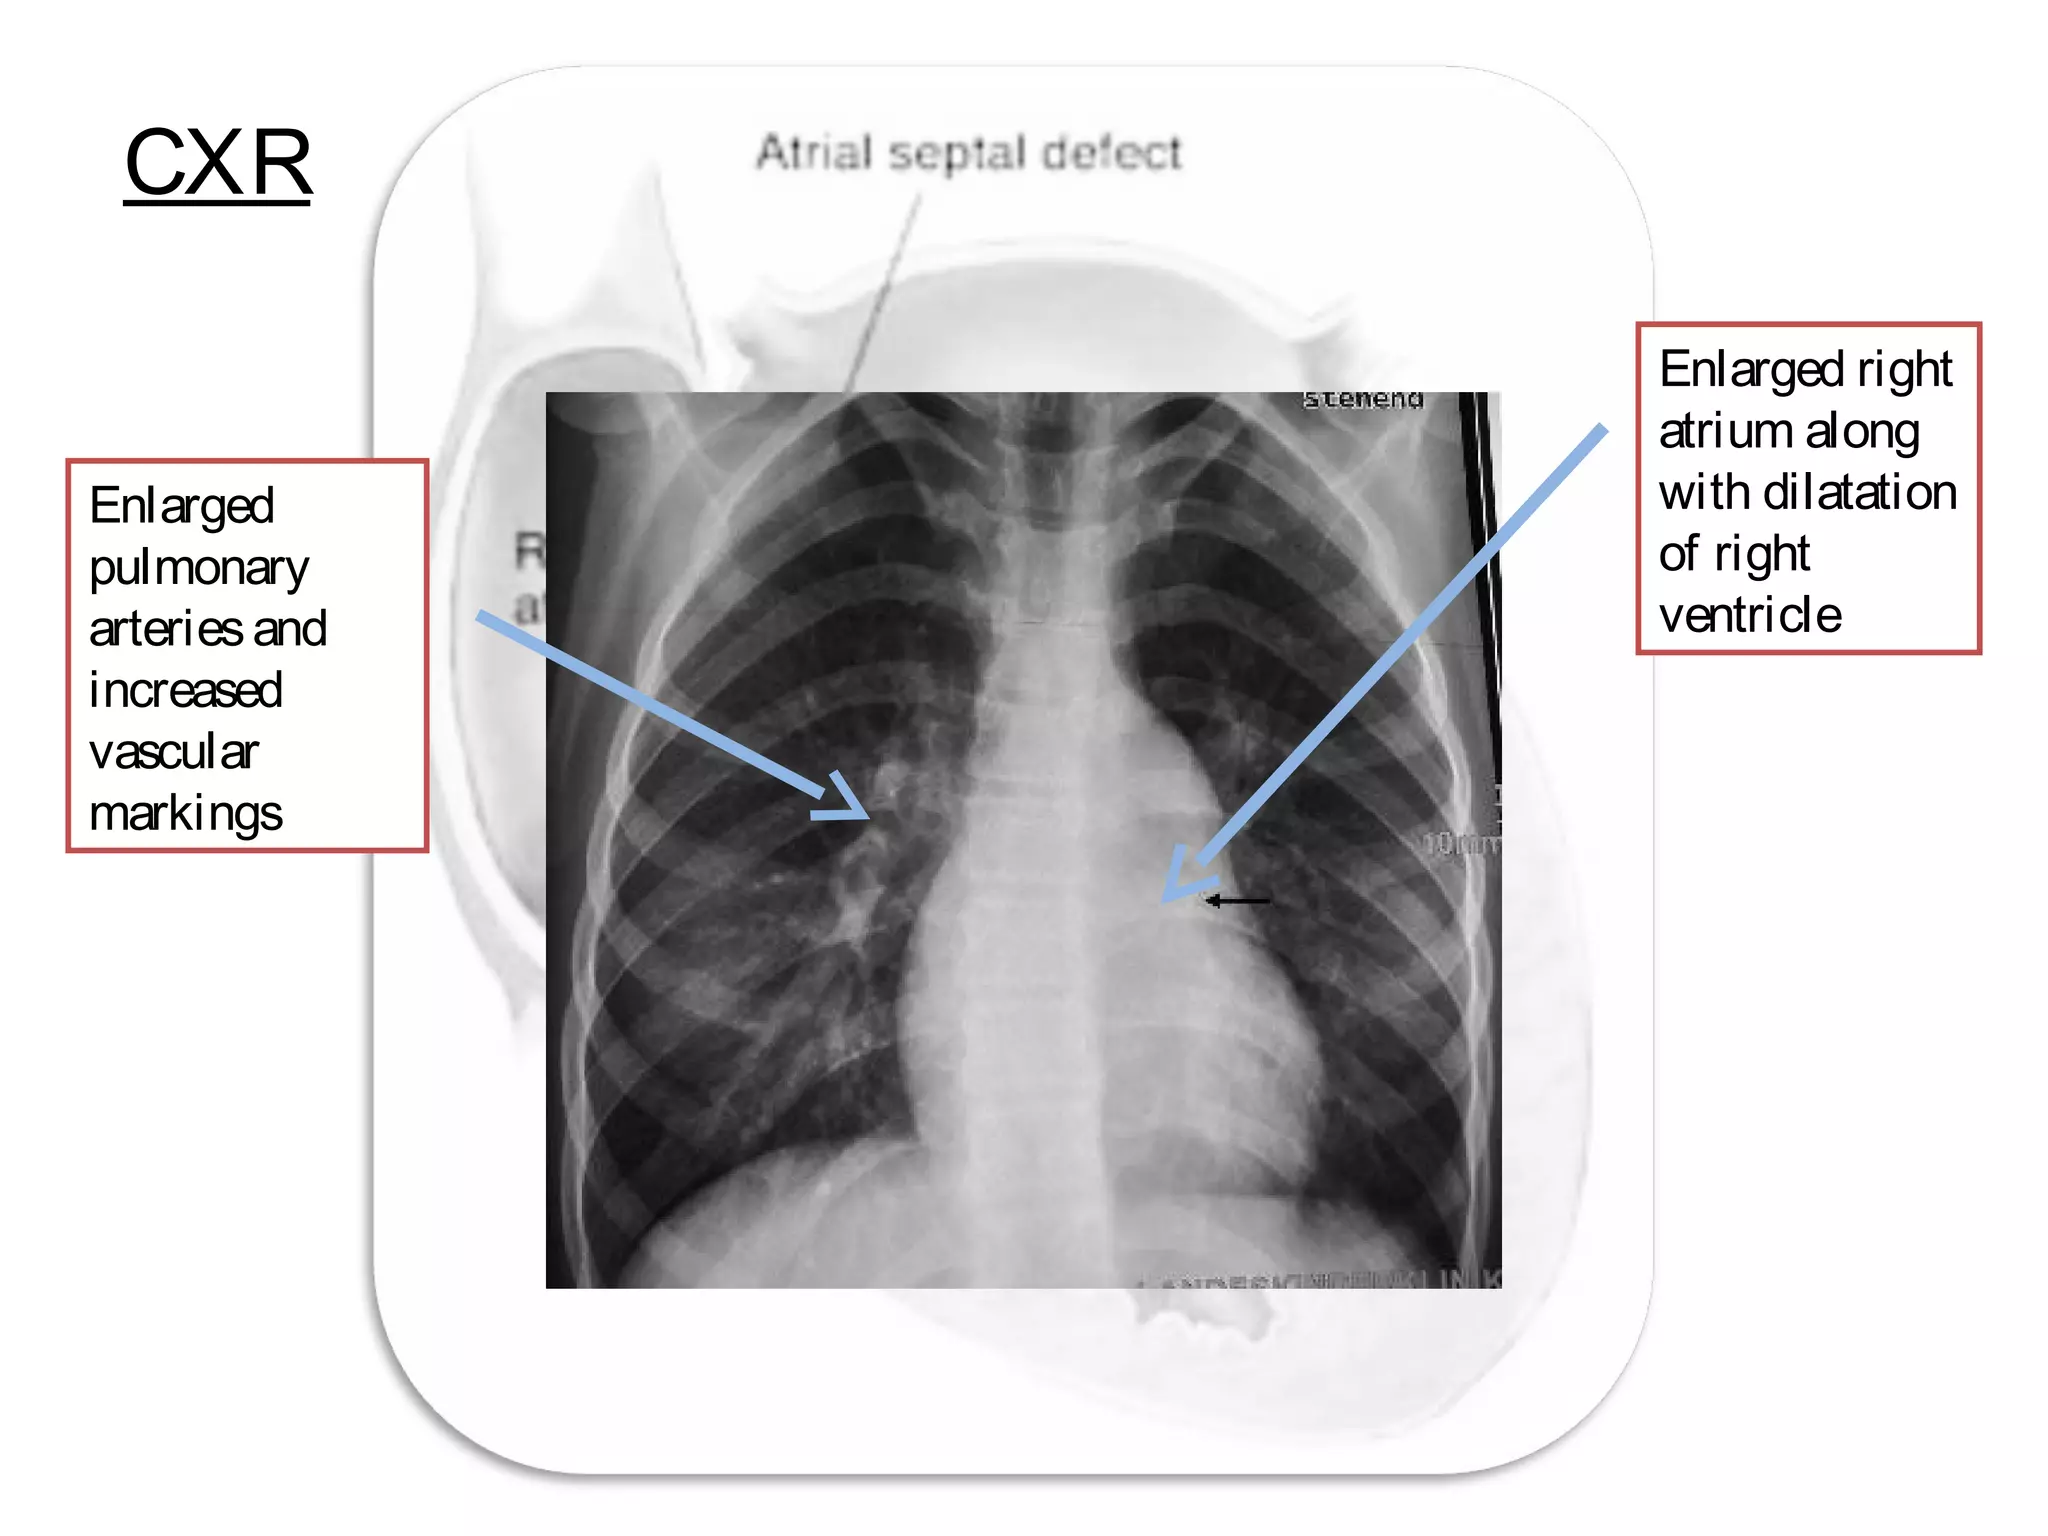

CXR

Enlarged

pulmonary

arteriesand

increased

vascular

markings

Enlarged right

atrium along

with dilatation

of right

ventricle